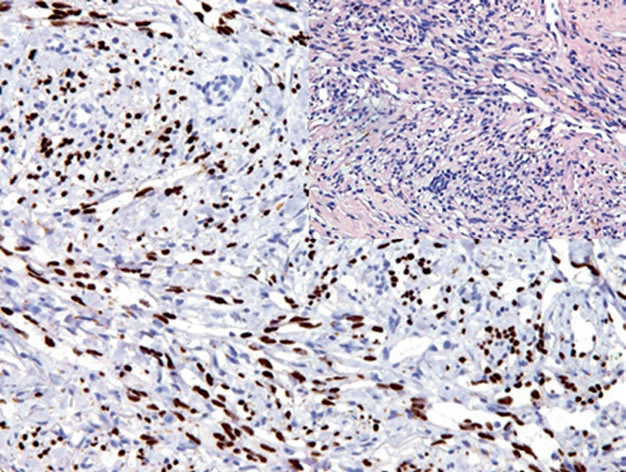

图片

Figure 3. Angiosarcoma, with strong nuclear expression of ERG in tumor cells.

In addition to endothelial cell tumors, ERG is also expressed in some immature hematopoietic cells. In prostate cancer with TMPRSS2-ERG translocation, ERG is positive. For mesenchymal tumors, some other mesenchymal tumors morphologically similar to vascular tumors also express this marker, such as solitary fibrous tumors, fibrous meningiomas, and epithelioid sarcomas. In certain types of lymphomas, a small number of cases also show ERG expression.